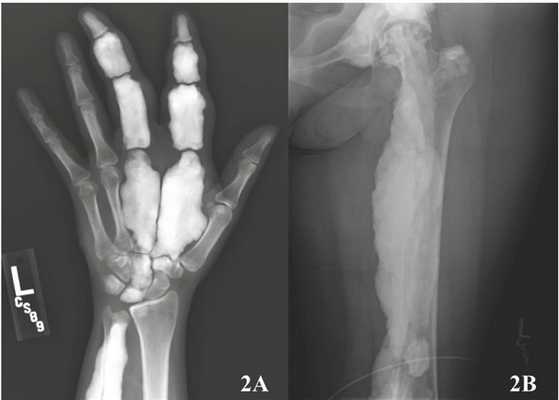

Рентгенография

Рентгенография считается модальностью достаточной для постановки диагноза.

Описано пять паттернов заболевания [1]:

- классический

- характерно утолщение кортикального периоста; во многих случаях встречается утолщение эндоста, особенно при дебюте в подростковом периоде

- толстые волнообразные бороздки в костной ткани по типу расплавленного воска, стекающего по свече

- ограничено склеротомом, может "переходить" через сустав на проксимальную/дистальную кость

Диагностика в основном основана на обычной рентгенографии. На рентгенограммах мелореостоз представлен как линейные поражения повышенной плотности кости вдоль большой оси (стволы или диафизы) трубчатых костей. Повреждения приводят к увеличению толщины коры и могут распространяться на внешнюю поверхность костей, создавая видимость «стекающего со свечи воска». При полиостатическом поражении линейные поражения, как правило, непрерывны вдоль одной и той же стороны пораженной конечности и «прыгают» через суставы. Может наблюдаться кальцификация мягких тканей и даже внематочная окостенение.

На рентгенограммах определяется остеосклероз и гиперостоз. Уплотнения костной ткани имеют вид продольных прерывистых или сплошных полос, что создает характерную картину «наплывов воска на свече». В соседних отделах конечности иногда выявляется нерезко выраженный остеопороз. Лечение симптоматическое. Проводится профилактика контрактур, при значительных деформациях выполняется хирургическая коррекция. Прогноз благоприятный.

Выявление патологии

Мелореостоз – болезнь, которую можно сразу выявить на рентгеновских снимках, в особенности, если у больного вторая или третья степень развития заболевания. Магнитно-резонансная томография (МРТ) является наилучшим вариантом для выявления болезни на первом этапе.

При наличии болезни Лери на снимке, полученном с рентгена, невооруженным глазом видно, что кость со всех сторон охватывает мутное пятно. Такие пятна бывают разных размеров, и часто захватывают окружающие мягкие ткани.